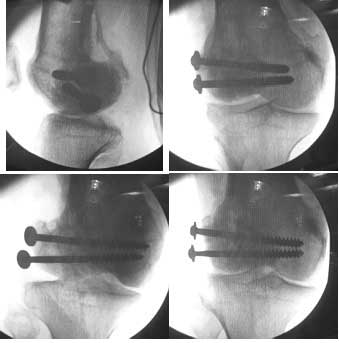

This was fixed temporarily, bone grafted with tricortical struts, and fixed by two cancellous screws. The fragment was not large enough to afford any fixation to a plate or such implant, and the screws held it compressed well to the rest of the distal femur.

Post-op - limb is well aligned, rom 0-30, but I am not pushing that right now, for the next two or three weeks.

Further plan - hope that the screws hold the fragment appropriately till union, but if the stability on table is anything to judge by, that should not be a problem.

Quadricepsplasty after a year or so, to restore flexion.

Pictures attached.

A good job, though personally I would have preferred the screws a bit longer.